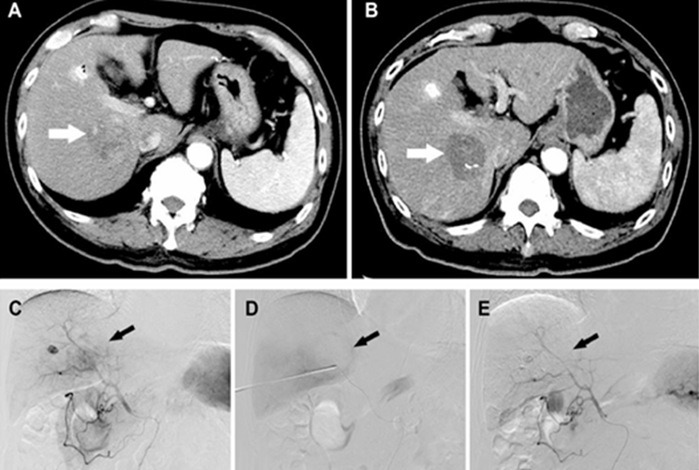

通过HAIC序贯TACE实现从“简单联合”向“时序重构”的升级,完善高肿瘤负荷患者TACE联合消融的治疗时序;同时推进新型介入栓塞材料的研发与转化应用,并建立TACE后系统性的肝功能保护策略,在强化控瘤的同时延缓肝功能衰退,为后续可重复介入和多模态联合争取窗口期。

l HAIC序贯TACE的临床应用及相关发表文章